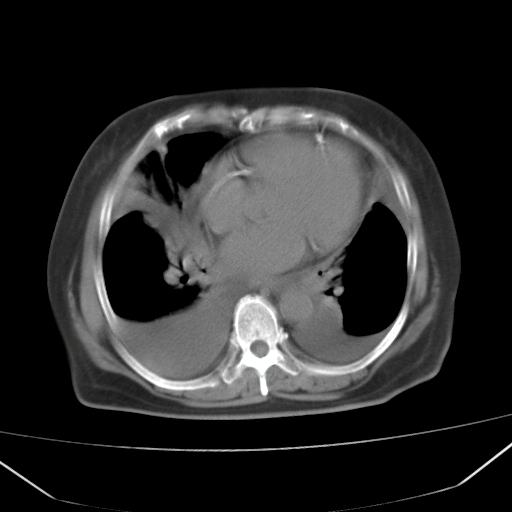

以下是引用liuyue在2008-4-19 22:25:00的发言:[br]先考虑:1.心衰伴肺水肿、双侧胸腔积液、叶间积液、双下肺不完全性肺不张; [br] 2.冠状动脉粥样硬化。

以下是引用lijuanln在2008-4-19 23:05:00的发言:[br]两侧胸腔积液,肺水肿[br]心包积液[br]提示心衰

以下是引用jiangjing在2008-4-20 10:43:00的发言:[br]结合病史支持 冠心病[冠状动脉钙化],心功能不全,肺淤血、肺水肿,双侧胸腔与斜裂积液